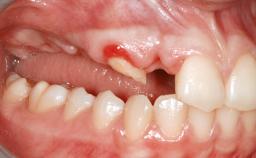

A 47-year-old woman who had suffered from aggressive periodontitis requiring a number of periodontal interventions over more than 10 years was referred by her general dental practitioner and periodontologist for bone augmentation and implant therapy. Her failing dentition had already been scheduled for extraction. The patient expressed a desire for implant-supported fixed restorations and esthetic improvement of her lower face. She had agreed to consult with a maxillofacial surgeon after the referring dentist had suggested bone augmentation. An initial examination by the maxillofacial surgeon revealed mobility of all residual teeth in a patient who was very unhappy with the function of her removable partial dentures. Due to periodontally migrated flaring teeth and loss of occlusal support, the vertical dimension of occlusion was dramatically reduced. The patient was displeased with her lower face because of deepened nasolabial, commissural, and supramental folds.

Soft Tissue Anatomy Intact Defective

Bone Volume Horizontally and vertically sufficient Horizontally deficient Deficient vertically or deficient vertically AND horizontally